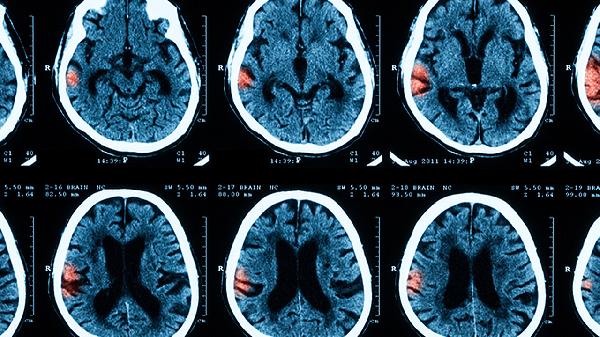

宝宝脑膜炎通常由细菌感染、病毒感染、真菌感染、寄生虫感染、结核感染等原因引起。脑膜炎主要表现为发热、头痛、呕吐、颈部僵硬、精神萎靡等症状,严重时可出现抽搐、昏迷。建议家长及时带宝宝就医,在医生指导下完善脑脊液检查、血常规等明确病因,并遵医嘱使用抗生素或抗病毒药物进行治疗。